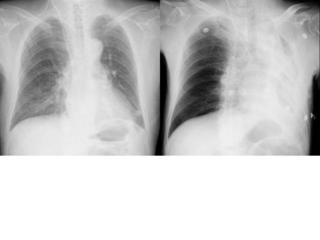

こちらを見て下さい。

わかりにくいかもしれませんが、このあたり。

気管が追いにくい、無くなっているようにも見えます。